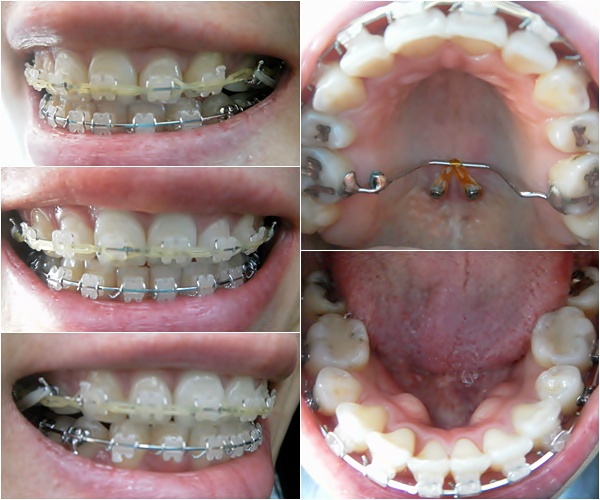

상악 파워체인만 새로 갈아 주었어요~ 이번 월치료는 간단하게 끝~ ^^

22번째 월치료~

상악 제일 안쪽 어금니 바이트 블럭 제거했어요~ 이번 월치료는 바이트 블럭 제거하는 걸로 진료 끝~ + _+

아~ 상악 4번 치아와 하악 7번 치아에 빨간보트 꼬무줄은 계속 열심히 걸어주고 있어요~

킬본교정 시작한지 아직 1년 6개월도 안 되었는데요~

돌출된 입도 쏙 들어 갔고~ 발치공간도 거의 다 닫혔고~ 치아도 가지런해졌고~ 벌써 이렇게 많은 변화가 ㅠㅠ